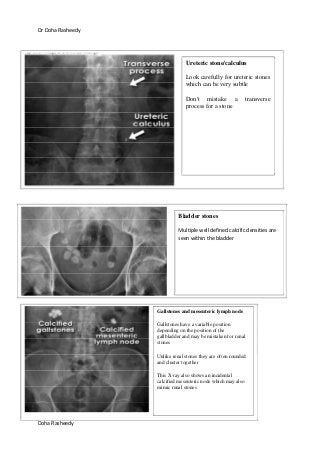

Ureteric stone/calculus

Look carefully for ureteric stones

which can be very subtle

Don't mistake a transverse

process for a stone

Bladder stones

Multiple well defined calcific densities are

seen within the bladder

Gallstones and mesenteric lymph node

Gallstones have a variable position

depending on the position of the

gallbladder and may be mistaken for renal

stones

Unlike renal stones they are often rounded

and cluster together

This X-ray also shows an incidental

calcified mesenteric node which may also

mimic renal stones